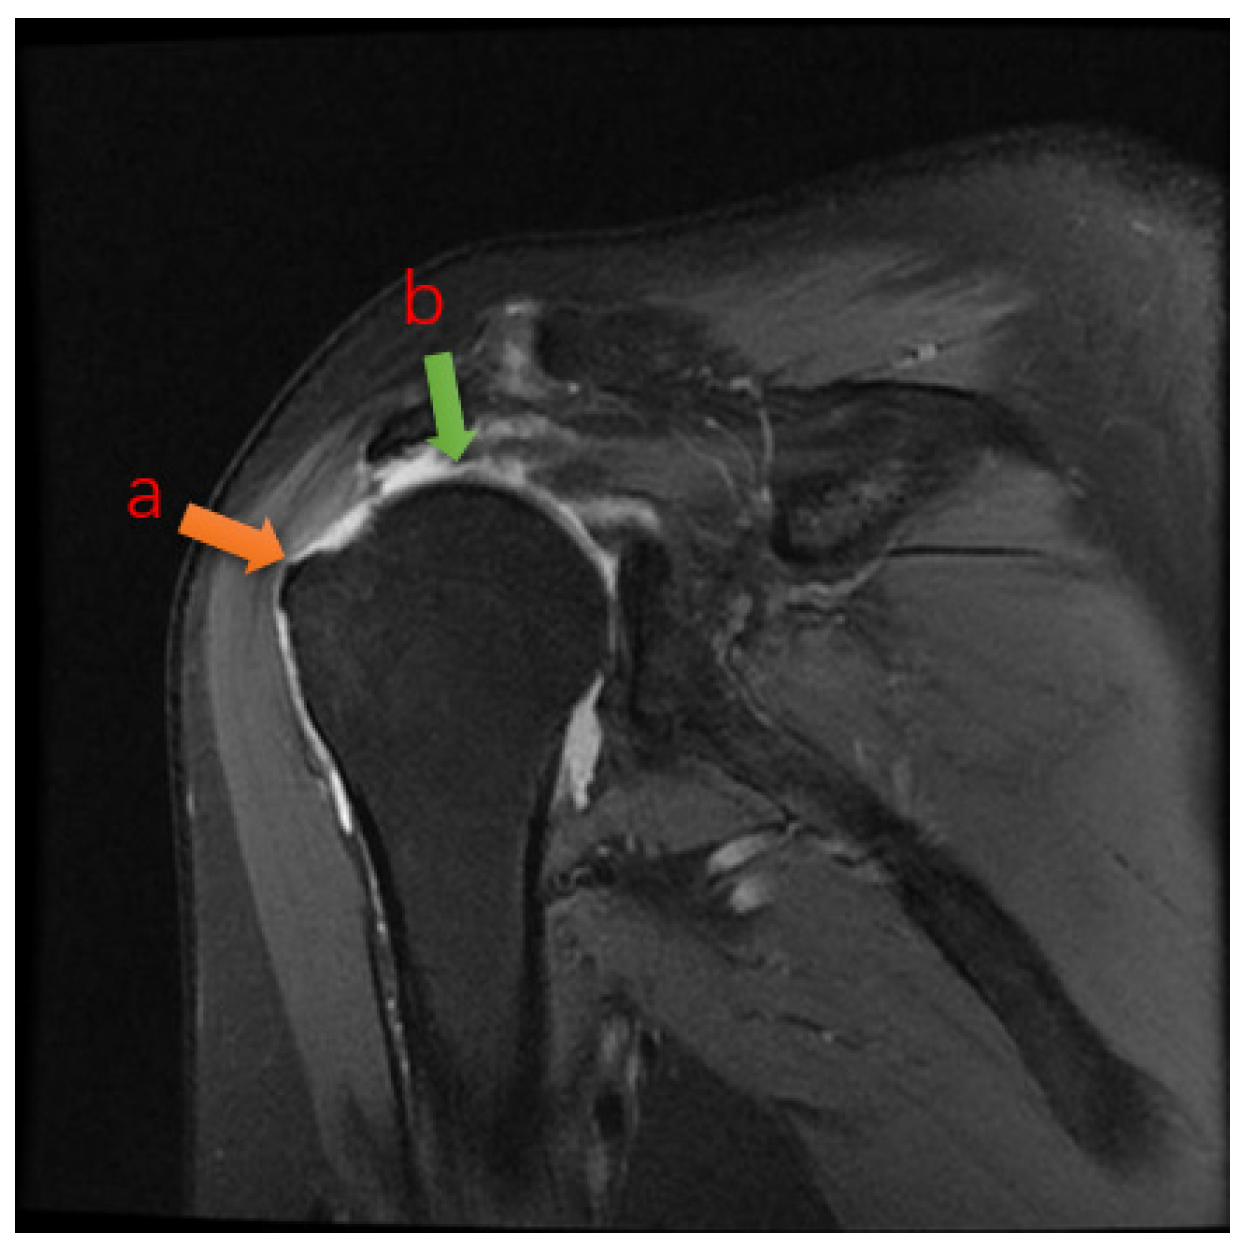

2.5. Automatic Segmentation of Predictions

Because the output of the deep neural network is two-channel, i.e., the output pixel points are predictively classified and assigned color values, it is possible to distinguish torn regions from normal regions by the difference in color values of the adjacent points [13]. Through continuous feedback learning, the deep learning network will give classification results for both color values, which can be evident within the software to see the segmented regions and boundaries (Figure 4), and thus be compared with the labels to calculate the relevant segmentation metrics [14]. In summary, the overall process of the segmentation algorithm is to first determine the approximate location of the torn region in the full image by the localization detection algorithm, and then to segment the torn region by classifying the pixel points into two categories, torn and normal, by operations such as convolution sampling classification.

Figure 4. Comparison between the physician-generated labels and the AI algorithm’s predicted segmentation results. The red regions represent manual segmentations by doctors, while the green contour outlines the AI’s predicted segmentation.